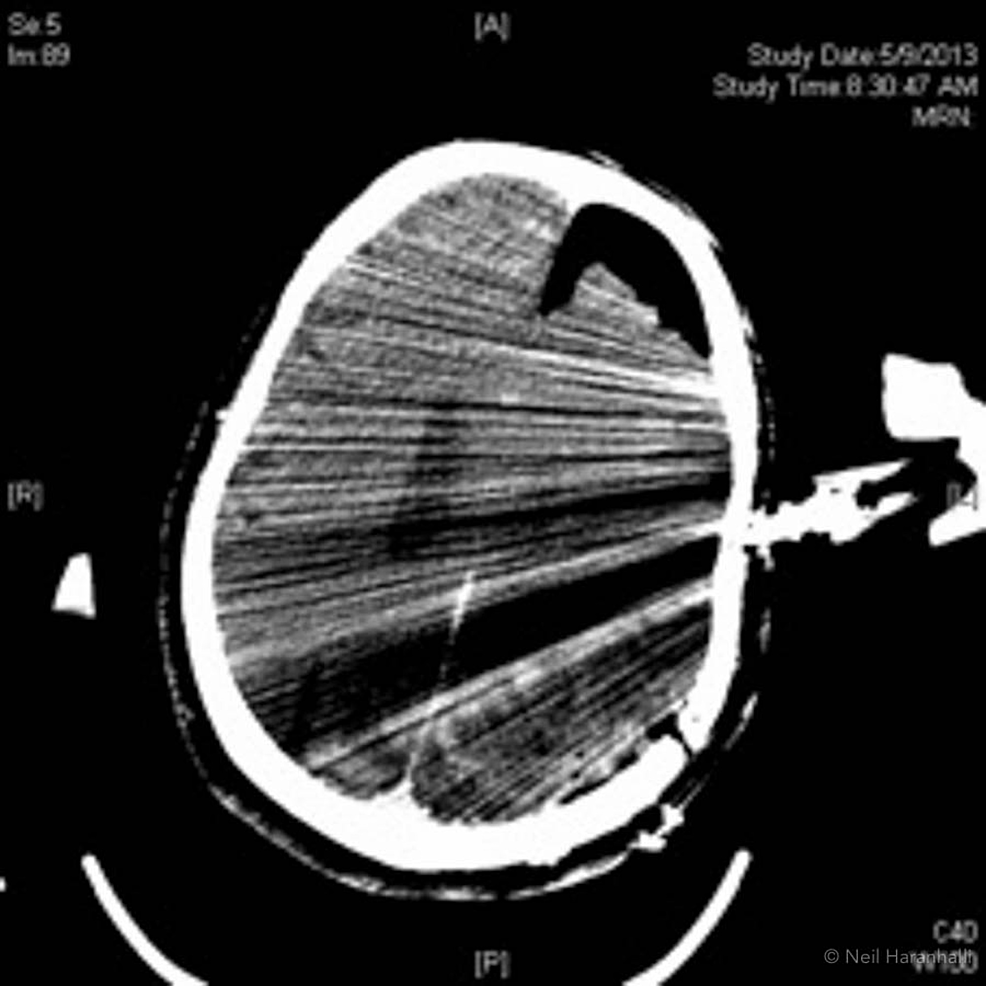

Reconstructed axial CT slice in an example subject showing motion Prominent Motion Artifact this article reviews the origins of motion artifacts and presents current mitigation and correction methods. important to recognize and understand motion artifacts to identify the physical cause of the problem in a particular. motion artifacts caused by breathing, cardiac movement, csf pulsation/blood flow create a ghost. in this review, we first examine the physical origins of. Prominent Motion Artifact.